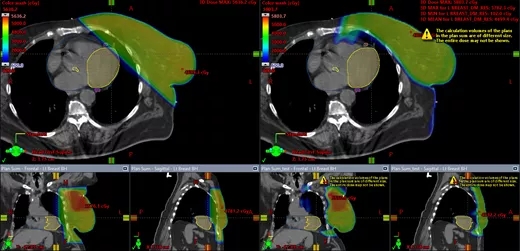

图2. 光子深吸气屏气(Ph-DIBH)与质子深吸气屏气(Pr-DIBH)的轴向、冠状和矢状图对比。可见质子治疗保护了左心室和左冠状动脉前降支(LADCA)。另外,可注意到Pr-DIBH照射的肺部体积显著减少。蓝色圆圈表示LADCA,黄色圆圈表示左心室